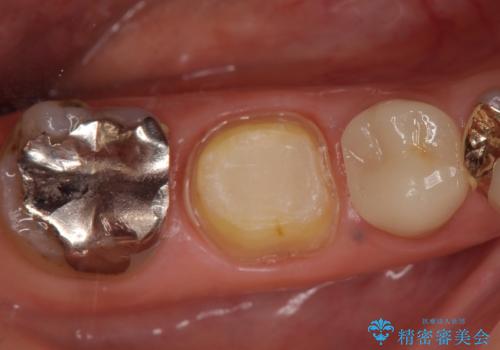

右下6は神経が死んでいたため根管治療を行い、オールセラミッククラウンによる補綴を行いました。

右下7は冷たいものがしみていたため、銀歯を除去後、オールセラミッククラウンによる補綴を行いました。

今回用いたオールセラミッククラウンはジルコニアフレームという白い素材の上にセラミックを盛っているため、審美性が非常に高いのが特徴です。

また、ジルコニアは人工ダイヤモンドの材料にも使われているほど高い強度を持っており、そのためオールセラミッククラウンは審美性だけでなく、奥歯やブリッジの補綴も可能とするクラウンです。